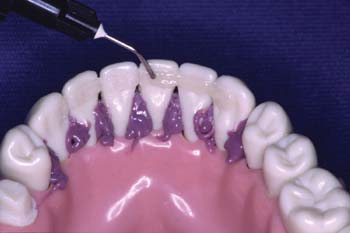

Técnica de estabilización y bloqueo opcional: Después del grabado dentario aplique vinil-polisiloxano en los espacios interproximales para bloquear estos espacios. Esto estabiliza los dientes durante la construcción de la férula y hace la limpieza más fácil. Las fotografías muestran instrucciones de esta técnica de bloqueo.

Aplique resina con relleno a los dientes. Aplique una capa delgada de resina translúcida y de viscosidad media a nivel de las áreas de contacto interproximales. Una jeringa Centrix hace que la aplicación sea más fácil. No polimerice todavía.

Adapte la fibra Ribbond. Sujete la fibra humedecida con unas pinzas de campo, posicione un extremo de la fibra en la resina sobre el diente. Presione la fibra a través del material con el dedo o un instrumento.

Adapte la fibra Ribbond en el contacto interproximal. Para evitar que la fibra ya adaptada se salga manténgala en su posición con un dedo o un instrumento. Coloque la fibra Ribbond lo más profundamente en los espacios interproximales con un instrumento. Continúe diente por diente hasta adaptarla en toda su longitud. No polimerice todavía.